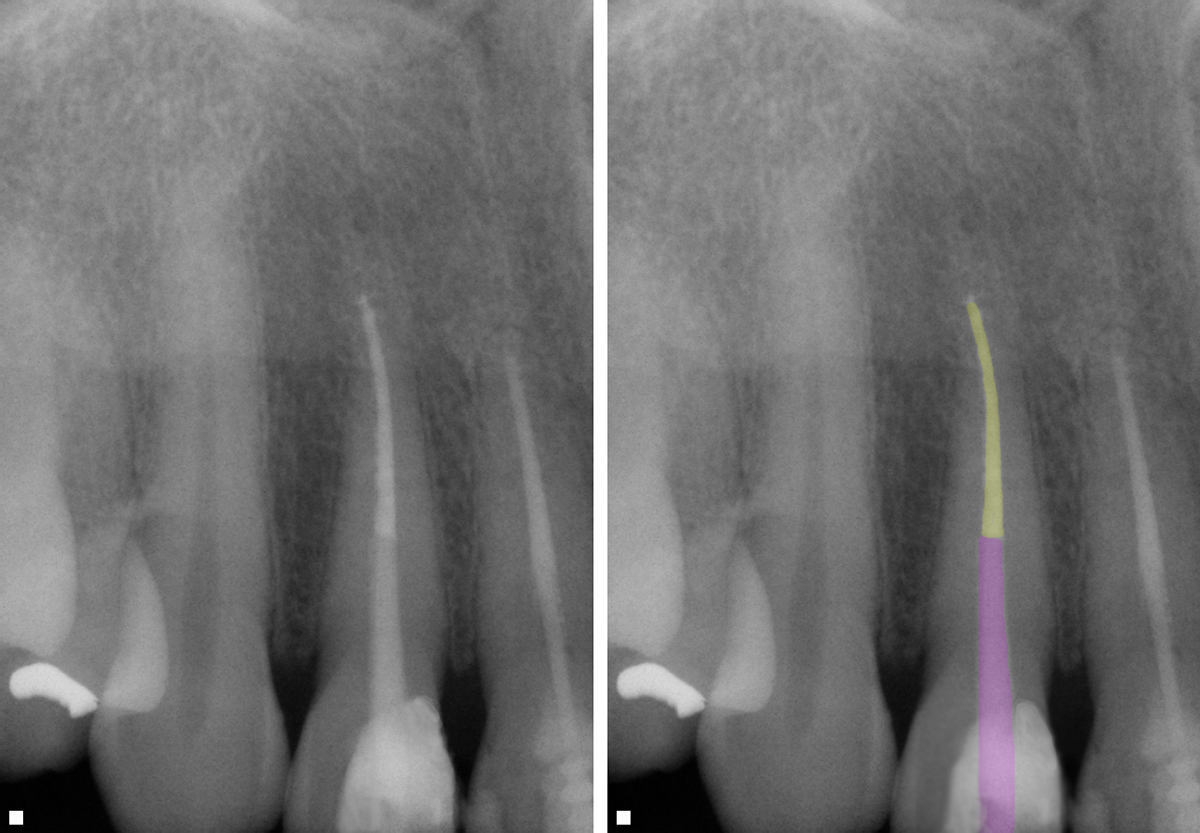

Endodontic sealer is considered to be more important than the core obturating material itself. Sealer with the least film thickness is favorable to minimize microleakage. When obturating the canal system, minimal sealer should be used, with the majority of the canal being filled with gutta-percha. Use of a single gutta-percha cone that matches the geometry of the final file used in the canal aids in achieving that goal.28 Additionally, with a single cone matching the last file used, the file by hydraulic force is able to drive the sealer into accessory anatomy that the irrigation protocol removed (Figure 10).

When extensive canal anatomy is present, as observed radiographically, warm vertical compaction may be a better obturation technique than a single-cone approach to achieve a 3-dimensional fill (Figure 11).29 In teeth with extensive canal anatomy, warm vertical compaction appeared to provide better sealing of the canal system than the single-cone obturation when dye penetration studies were performed on extracted teeth.30 Therefore, selection of obturation technique should be based on anatomy of the canal system as well as size of the apical half of the canal. Canals that offer some "tug-back" on a cone that matches the final file size can be predictably obturated with a single cone, whereas when there is no tug-back and shortening the cone at the apical end does not achieve that, a warm vertical compaction should be selected.

Fig 11. Canal completely obturated using a combination of single cone on the apical (yellow) and warm compaction on the remaining canal space (purple).

Figure 11

Fig 16. Fiber post has been prepared to match the final file size, conserving cervical tooth structure and luted into the canal with a dual-cure resin adhesive cement (yellow: obturation, purple: fiber post).

Figure 16